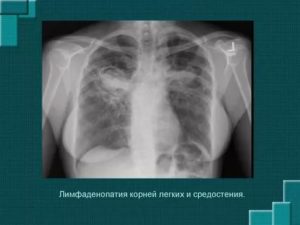

Изменения на снимках компьютерной томографии

Во врачебной практике часто диагностируется лимфаденопатия корней легких, которая может быть односторонней или двухсторонней. Укрупнение корней легких является сигналом о том, что присутствуют метастазы в другие органы или системы. Поэтому очень важно провести ряд лабораторно-инструментальных исследований.